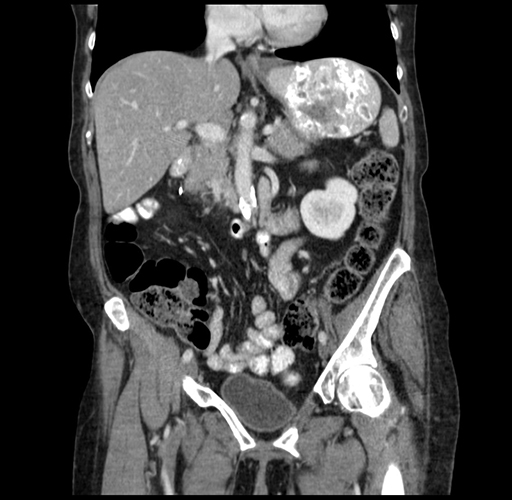

Pre-Chemo: Axial Venous

Axial Venous